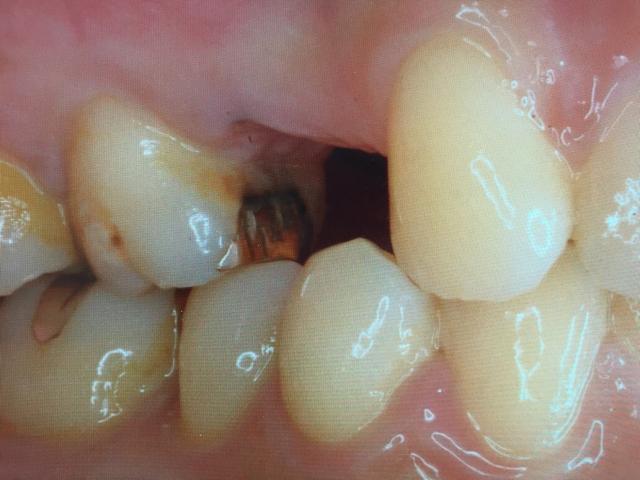

2015.07.18 [ インプラント症例 ]

左下6、7番目のインプラント手術

今回も良くあるケースです。